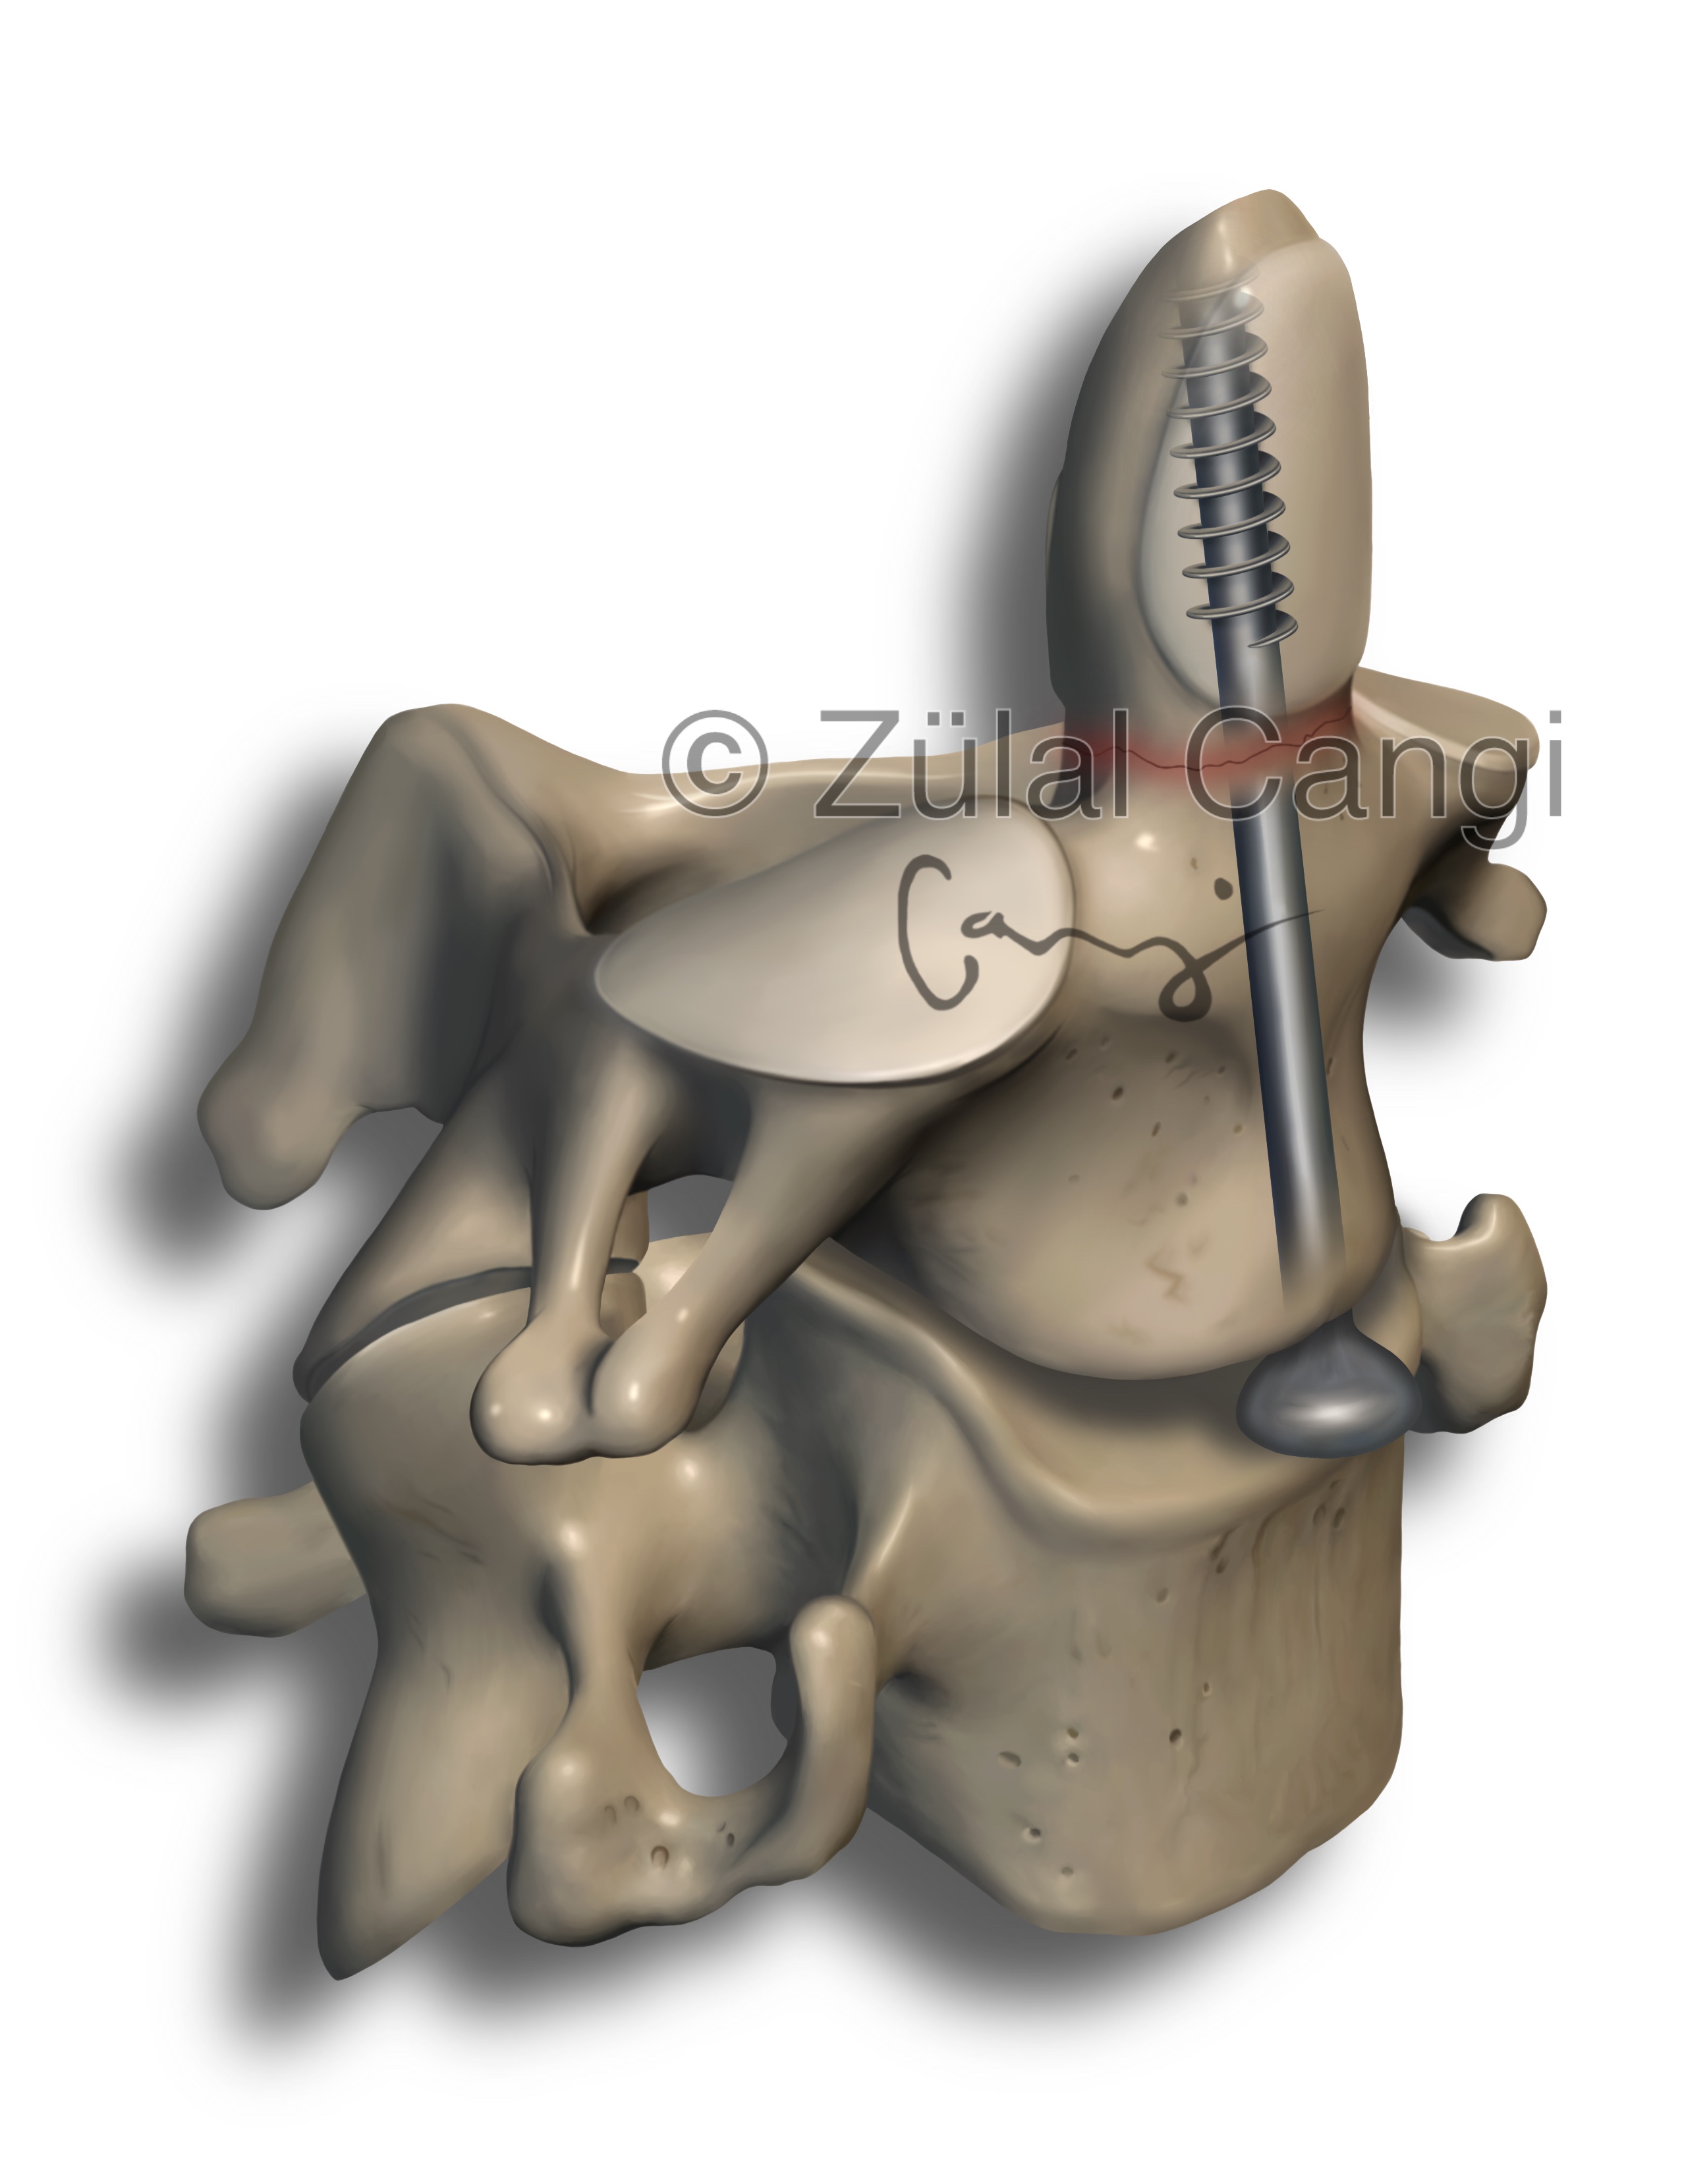

Sanatın estetiğini bilimin kesinliğiyle bir araya getiren Zülal Cangi, medikal ve bilimsel illüstrasyon alanındaki çalışmalarıyla akademik yayınlar, eğitim materyalleri ve çeşitli bilimsel platformlar için görsel içerikler üretmektedir. Amacı, bilimsel bilgiyi yalnızca doğru biçimde aktarmakla kalmayıp, aynı zamanda öğretici ve estetik bir dille görünür kılmaktır.

PORTFÖY